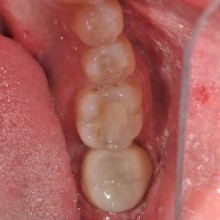

The crown was then designed in 5 to 10 minutes using the Planmeca software, after which it was milled in approximately 20 minutes. The crown was cleaned and polished, then tried in the mouth to confirm its fit. Because of the accuracy of the True Definition scanner, no adjustments were necessary. The tooth was then isolated and 3M™ ESPE™ Scotchbond™ Universal Adhesive was applied. The bonding surface of the restoration was sandblasted and cleaned, and then cemented with 3M™ ESPE™ RelyX™ Ultimate Cement.

Conclusion This case is a typical example of how seamless the process of scanning an impression and designing and milling a same-day restoration in the office can be. In my practice now, the time from completing the scan to cementing the crown is approximately 40 minutes. Using this technology, we can accomplish in one short visit what used to take a week or more. Patients receive their final restorations quickly and with a more comfortable procedure, and dentists are able to work with confidence knowing that crowns fit with outstanding accuracy.